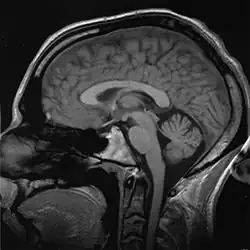

Puede, o no, ser posible alcanzar una realización científica final involucrando la posibilidad del libre albedrío adentrándonos en los orígenes de nuestros pensamientos conscientes. En el punto de vista científico, toda experiencia consciente es contingente hacia las neuronas —un golpe fuerte en la cabeza puede servir como demostración a este punto, así como casos documentados de lesiones neurológicas.[43] El cerebro consiste en miles de millones de neuronas, con mil billones de conexiones entre ellas. En un nivel bioquímico, la tarea principal de una neurona es propagar impulsos electro-químicos a otras neuronas formando un “circuito integrado” que constantemente recibe información de los sentidos (vista, olor, tacto y gusto) y devolviendo información para controlar músculos y órganos. Solo el 10 % de las neuronas en el sistema nervioso tratan con los impulsos sensoriales y con el control de músculos; las neuronas sobrantes sirven para integrar, refinar y procesar señales de entrada o salida.

La experiencia del libre albedrío es así conceptualizada surgiendo de alguna combinación de estas neuronas, pero ¿cómo llegamos a esta acumulación de neuronas, que son finos hilos de grasa con el potencial de recibir impulsos eléctricos, pueden dar poder a nuestro consciente, emociones y sentimientos? ¿Cómo puede ser que este concepto de “yo” y nuestro libre albedrío puede controlar neuronas y nuestro comportamiento, y el cerebro es meramente una sopa tibia de grasa, colesterol y neurotransmisores? Este misterio sin resolver domina el debate moderno sobre la existencia de nuestra conciencia y la posibilidad del libre albedrío.

En los años 1970, Libet estuvo involucrado en los estudios de la actividad neural y la "sensación de umbral". Estas investigaciones trataban de determinar la secuencia de activación en sitios específicos del cerebro requerida para desencadenar acciones voluntarias tales como el pulsado de un botón, utilizando equipos electroencefalográficos. Un famoso experimento —luego reproducido muchas veces por otros grupos— demostró que eventos cerebrales inconscientes (observables como potenciales eléctricos, llamados potenciales de preparación [en inglés readiness potential]) realmente preceden en un lapso variable (de 0.3 hasta varios segundos) la sensación consciente de haber tomado una decisión voluntaria en preparación de una acción motora —como el pulsado de un botón—.

Ahora bien conocido en neurología, el llamado 'Bereitschaftspotential' (BP en idioma alemán, 'readiness potential' en inglés), también llamado 'potencial premotor, es una medida de la actividad en el córtex motor y el área motora suplementaria en el cerebro ocupado en la preparación de un movimiento muscular voluntario. Es una manifestación de la contribución cortical al planeamiento del movimiento voluntario. Fue registrado y reportado ya en 1964 por Hans Helmut Kornhuber y Lüder Deecke en la University of Freiburg en Alemania. La publicación completa apareció en 1965 luego de muchos experimentos usados como control.[44]

Estas observaciones indican que los procesos neurológicos inconscientes preceden y potencialmente causan tanto la sensación de haber realizado una decisión por propia voluntad como el mismo acto motor.[45]

La conclusión derivada por Libet de estas observaciones es que los procesos cerebrales determinan las decisiones, luego percibidas como propias subjetivamente por el mismo cerebro a través del fenómeno de la consciencia (awareness). Libet solamente considera como posible la idea de libre albedrío en su noción de veto —la capacidad de la actividad consciente para bloquear o abortar un acto ya iniciado—, bloqueo posible gracias al tiempo restante de algunos cientos de milisegundos entre la percepción subjetiva de la decisión y la ejecución del acto mismo. Aunque el autor no parece adherirse a esta idea. El problema, como señala John N. Gray, es que no podemos saber cuándo utilizamos el veto, por lo que nuestra experiencia subjetiva es siempre ambigua.[46]Neurología y psiquiatría